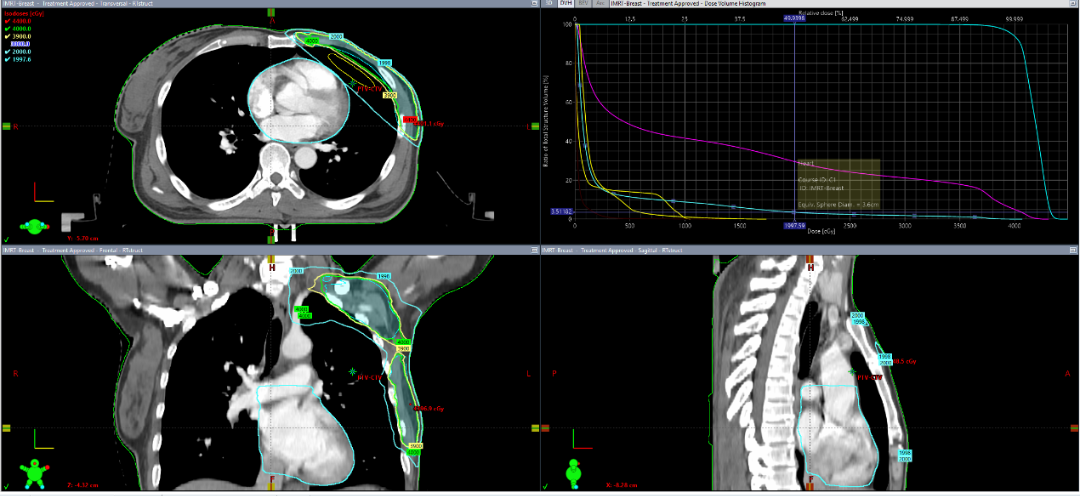

乳腺癌已经成为女性最常见的恶性肿瘤,而且近年来发病人群逐渐年轻化。乳腺癌的治疗一直都是肿瘤综合治疗的典范。大量随机对照临床研究证明:无论是保乳术后还是改良根治术后,放射治疗都能够明显降低局部区域复发并改善长期生存。 随着放疗技术的明显进步,传统放疗年代担心的心脏及肺损伤已经明显降低,最新的研究已经证明在新的放疗技术条件下(IMRT/VMAT)左侧乳腺癌术后放疗并不会明显增加心、肺损伤。分割模式为常规分割,50Gy/25-28次,大概在5-6周完成。 2000年左右,欧美国家开展了一系列保乳术后大分割放疗的临床研究,结果显示3周大分割放疗(40-43.5Gy/15-16次)在保证疗效相同的前提下毒性反应还略有减轻,更关键的是明显缩短了治疗时间,降低了医疗费用。 国内中国医学科学院肿瘤医院开展的全乳大分割放疗及改良根治术后放疗的3期临床研究也得出了同样的结果,已经分别在肿瘤顶尖杂志JCO及LANCET oncology上发表,证明3周放疗同样适合于亚洲人。 协和放疗科于2019年在福建省内率先开展乳腺癌术后大分割放疗,无论是保乳术后,还是改良根治术后大分割放疗(15-19次)均接受度高,心肺剂量降低(图1)。并于2021年7月全面推广。截止2023年2月,我院放疗科乳腺癌术后大分割放疗患者总数超过1000例。 随着最新的FAST-Forward研究结果发表,放疗科又在杨勇主任的带领下将保乳术后放疗时间又由3周缩短到1周(5次完成),明显减少患者在院时间,节约医疗费用,降低医保成本。 自2022年下半年,在DIBH技术支持下,福医协和的超大分割放疗顺利开展。相信2023年在放疗科全体员工的努力下能够给更多乳腺癌患者提供比肩欧美的优质放疗。 ▲左侧保乳术后2600cGy/5f,肺V8=12.5%(要求<15%), 心脏V1.5=9.16,V3=5%,心脏和肺受量极低 ▲右侧保乳术后超大分割放疗,肺V8=8.63%(要求<15%)

▲乳腺癌改良根治术后大分割放疗,心脏Dmean=278cGy,肺V20<30%,心肺剂量低